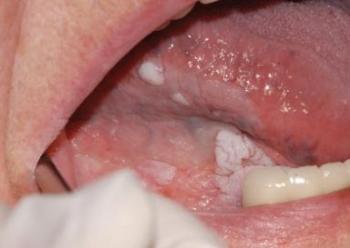

White sponge naevus

Családi halmozódást mutató, gyorsan leváló hámmegvastagodás (10.14. ábra)

10.14. ábra. White sponge naevus (leukokeratosis exfoliativa mucosae oris)

(Gera I. felvétele)